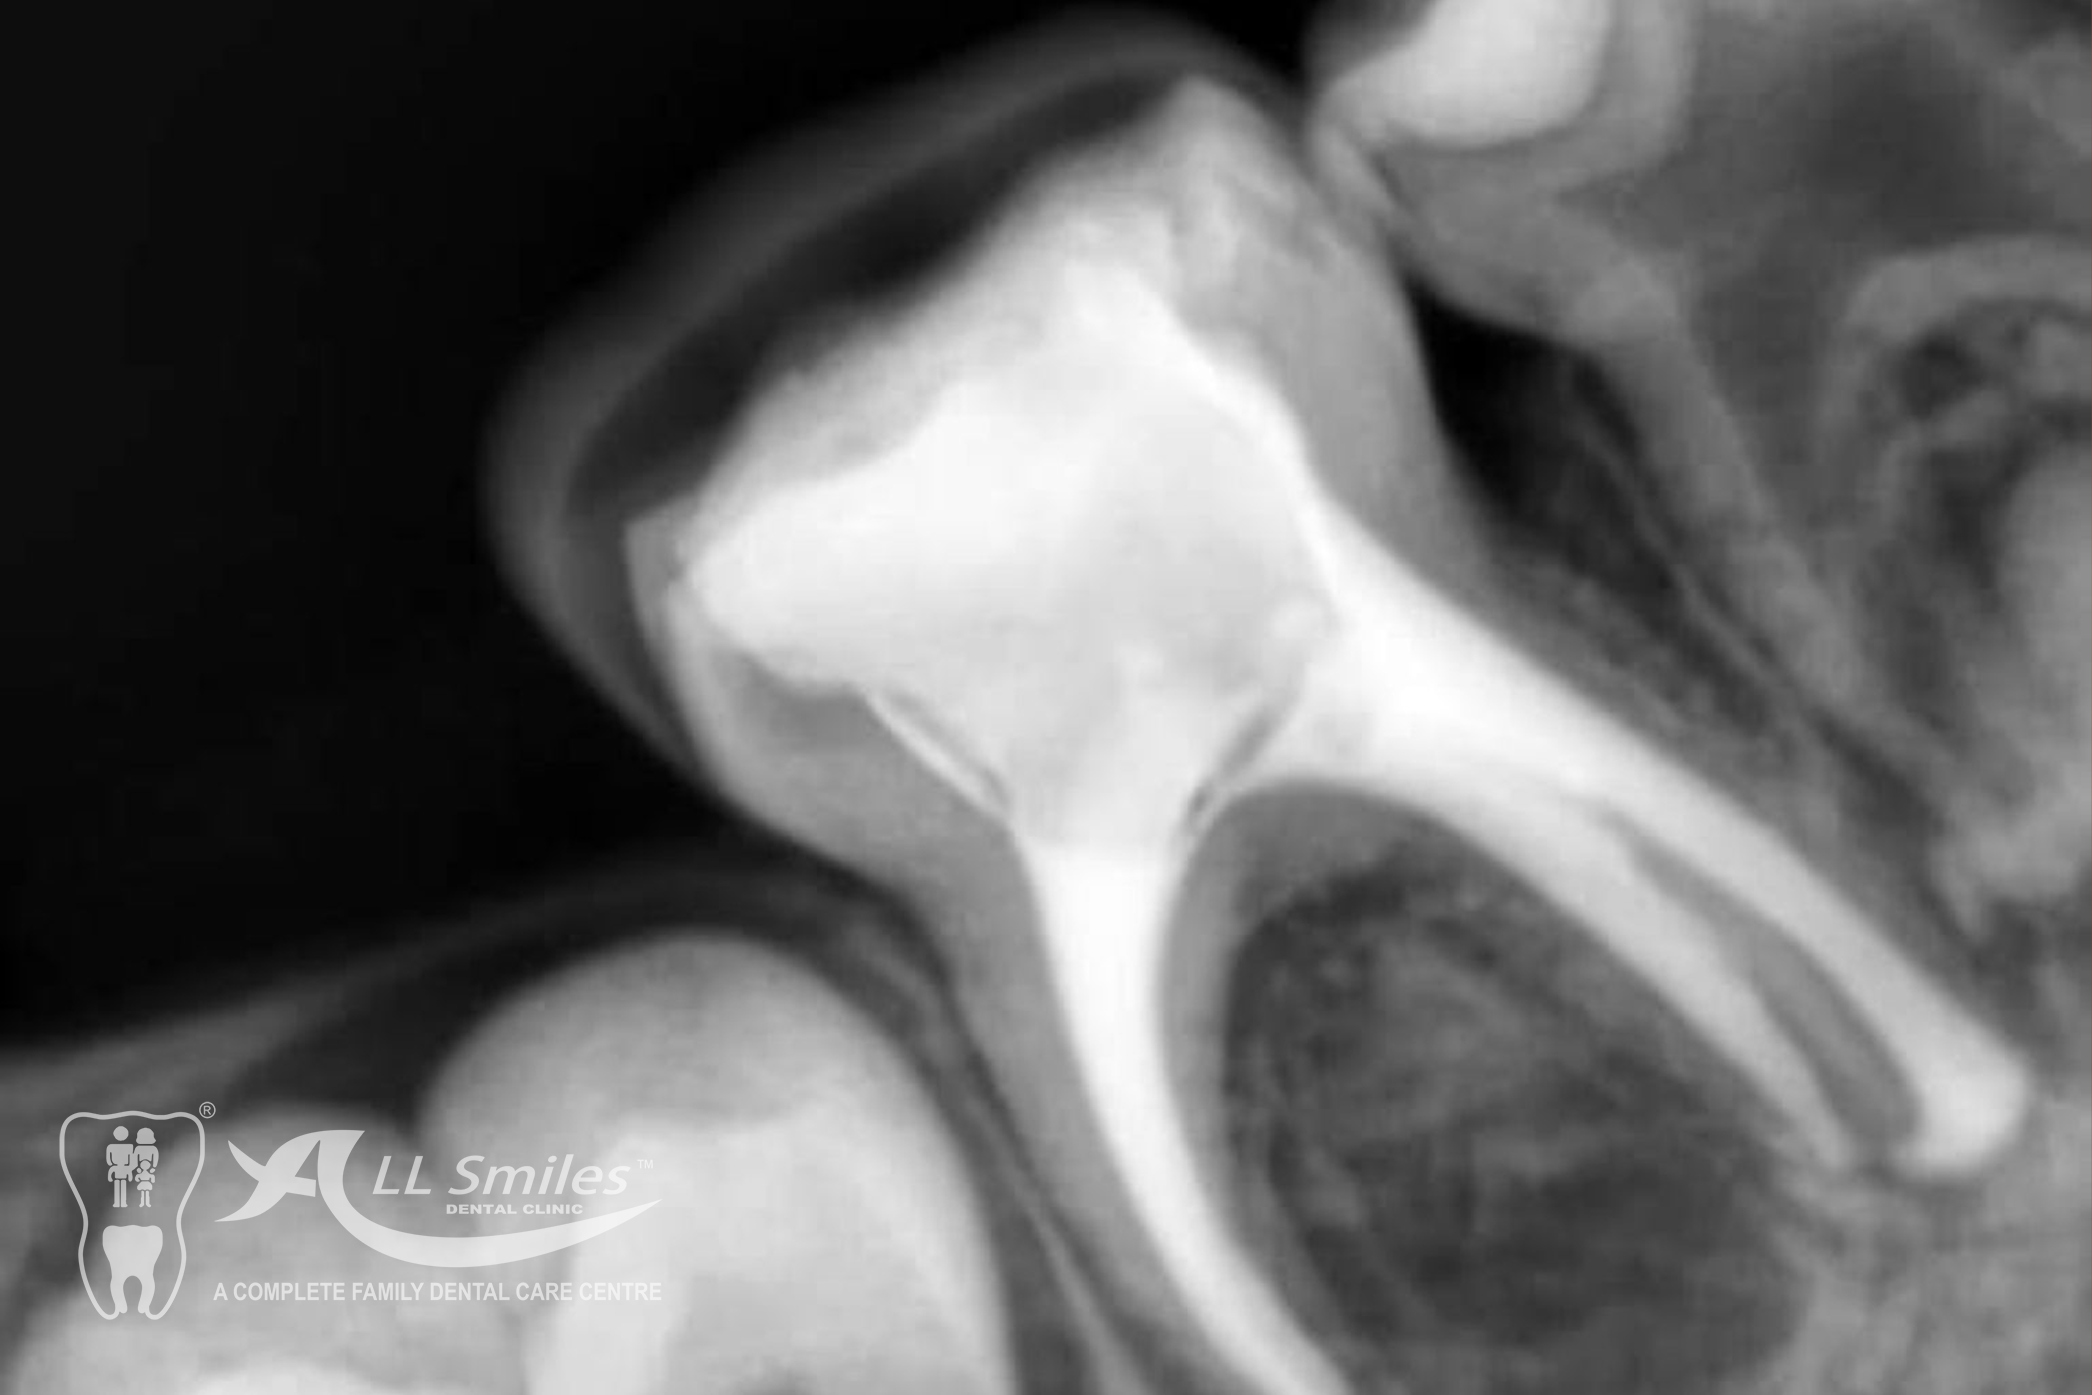

If a child has a cavity, the dentist will remove the decayed portion of the tooth and fill the space with a dental filling. Fillings can be made of various materials, such as composite resin or glass ionomer, depending on the specific needs of the child.

These are treatments performed on baby teeth to save them from extensive decay or infection.

Crowns are tooth-shaped caps that cover and protect damaged or weakened teeth. They are commonly used for baby teeth that have extensive decay or are at risk of fracture.

Child Dentistry Gallery

Yes, dental X-rays are generally safe for children. The level of radiation exposure is minimal, and dentists take necessary precautions to minimize radiation and ensure safety.